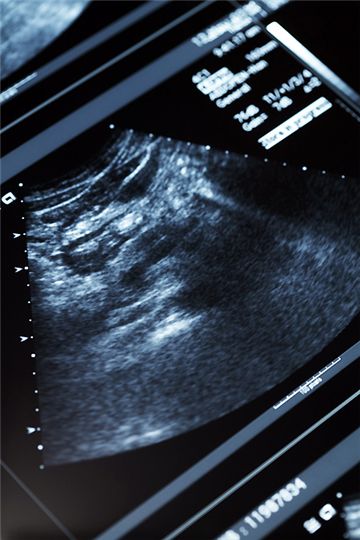

[아시아경제 박승규 기자] 최근 보건복지부와 보건사회연구원에서 발표한 ‘2012년 전국 결혼 및 출산 동향 조사’에 따르면, 피임을 하지 않지 않았음에도 1년 이상 임신을 하지 못한 기혼여성(20~44세)이 969명 중 32.3%로 나타났다. 이는 3명 중 1명에 해당하는 높은 수치로 볼 수 있다. 연령을 세분화해서 살펴보면, 24세 이하의 난임률은 19.2%, 25~29세는 14.2%, 30~34세는 22.9%, 35~39세는 49.3%, 40~44세는 71.9% 순으로 나타났으며, 대부분 나이가 들어감에 따라 난임률이 상승하는 것으로 조사됐다. 또 직장에 다니는 기혼여성의 난임률이 높은 것으로 나타났다. 직장 여성의 경우 36.0%, 그렇지 않은 여성의 경우 29.3%로 집계됐다. 한편 난임의 원인에 있어 우선 여성의 경우, 나팔관 장애(19.3%), 배란장애(16.7%), 자궁내막 장애(10.8%) 순이었다. 남성의 경우에는 정자무력증(10.4%), 무정자증(8.5%) 등이 나타났다. ◆ 난자도 나이를 먹는다, 치료 빠를수록 좋아 = ‘나이’가 들면서 가임 능력이 감소되는 것은 생물학적으로 어쩔 수 없는 사실이다.30세 이하의 여성이 한달 중 임신이 되는 가능성은 약 20%이지만, 40세 이상의 여성이 수태할 가능성은 약 5%정도로 추산된다. 시험관아기시술 등 불임치료법을 사용하는 경우에도 40세 이상의 경우 수정 능력의 변화와 함께 난자의 기능도 저하되기 때문이다. 따라서 난임(불임)의 극복을 위해서는 불임진단을 받는 것이 우선시되며, 1개월 내외로 진단이 끝난 경우에는 바로 치료를 받을 것을 전문의들은 권한다. 불임치료에는 과배란유도 및 자궁강내인공수정이나 생식체난관이식(GIFT), 시험관아기(IVF) 등이 꼽힌다. 서울대학교산부인과 불임클리닉 문신용 교수는 “여성의 나이가 40세에 가까워짐에 따라 골반염즘, 자궁내막증 등 가임 능력을 떨어뜨리는 질환이 발생할 확률이 높다”며, “에스트로젠과 프로게스테론은 자궁내막이 정상적으로 발육해서 초기의 태아가 정착할 수 있도록 하는데 필수적인데, 노화로 인한 난소로부터의 호르몬 감소는 임신에 있어 많은 영향을 준다”고 설명했다.